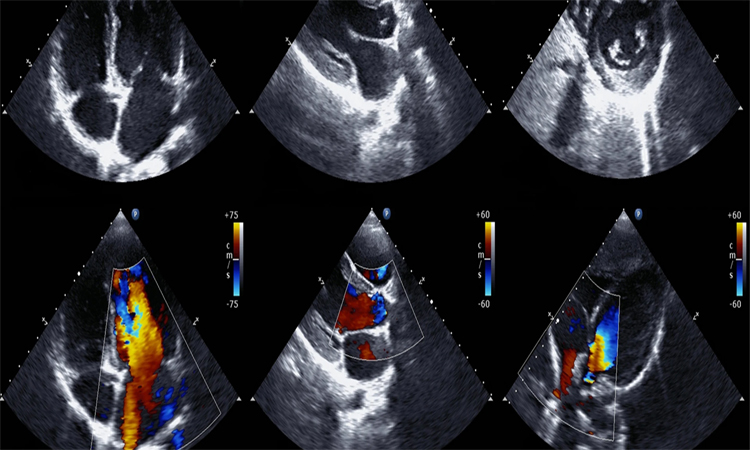

An echocardiography, echocardiogram, cardiac echo or simply an echo, is an ultrasound of the heart. It is a type of medical imaging of the heart, using standard ultrasound or Doppler ultrasound.